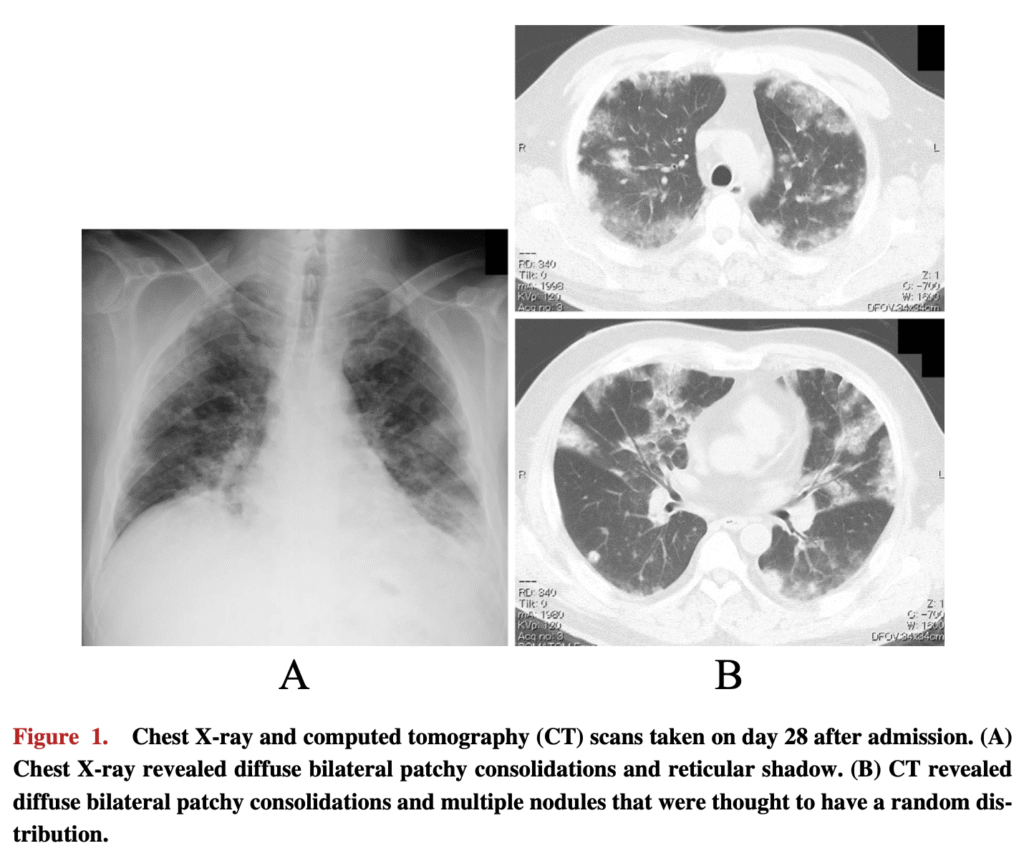

画像所見

49例を含むシリーズでは、胸膜下に多発する網状結節性浸潤影すりガラス陰影を伴うびまん性の両肺浸潤影など慢性好酸球性肺炎の一致する所見が認められた。しかし、急性好酸球性肺炎の特徴である胸水貯留も3分の2の症例で認められた。

74症例の最近のシステマティックレビューでは、43例にBALが行われ、好酸球数の中央値は20.5%(IQR 10.5-20.5、幅 0-98%)だった。両側の浸潤影が68.1%、すりガラス陰影が41.7%、斑状の浸潤影が30.6%、末梢優位の陰影を19.4%に認めた。ダプトマイシンの投与量は中央値6mg/kg(IQR 6.0-7.9)。症状はダプトマイシン投与開始から中央値19日(IQR 12-24)で出現した。末梢血の好酸球上昇は86.5%に認めた。治療はダプトマイシン中止のみが27%、投与中止かつグルココルチコイド投与は51.4%であった。96時間以内に87%の患者が改善を認めた。